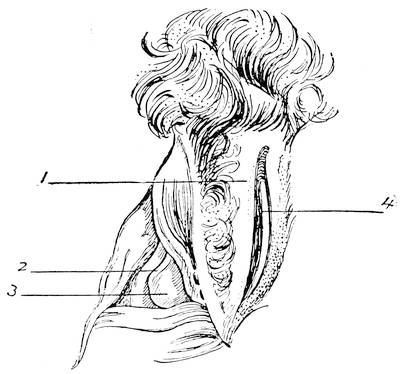

Mons of Venus, labia majora, minora, vestibule, bulbs, clitoris, Bartholinian glands, hymen, vagina, uterus, broad and round ligaments, viiitubes, ovaries, Graafian follicle, ovum.

F. The Female External Genitals

In the female the vestibule, or the shallow depression which was formed through the breaking through of the urogenital membrane, remains open throughout life, and is termed the vestibule of the vulva. From the sides of the lower part of the sinus a pair of evaginations are formed and give rise to the Bartholinian glands. The vestibule being in fact the open sinus urogenitalis, the urethra and the vagina naturally have their orifices in the same.

The genital tubercle ceases to grow in the female and becomes the clitoris. The genital folds or the lips of the vestibule become prolonged and form the labia minora or the nymphae. The genital swelling increases in size through adipose and fibrous tissue. The part situated on the ventral side of the clitoris becomes the mons veneris, while the lateral parts are converted into the labia majora of the vulva.